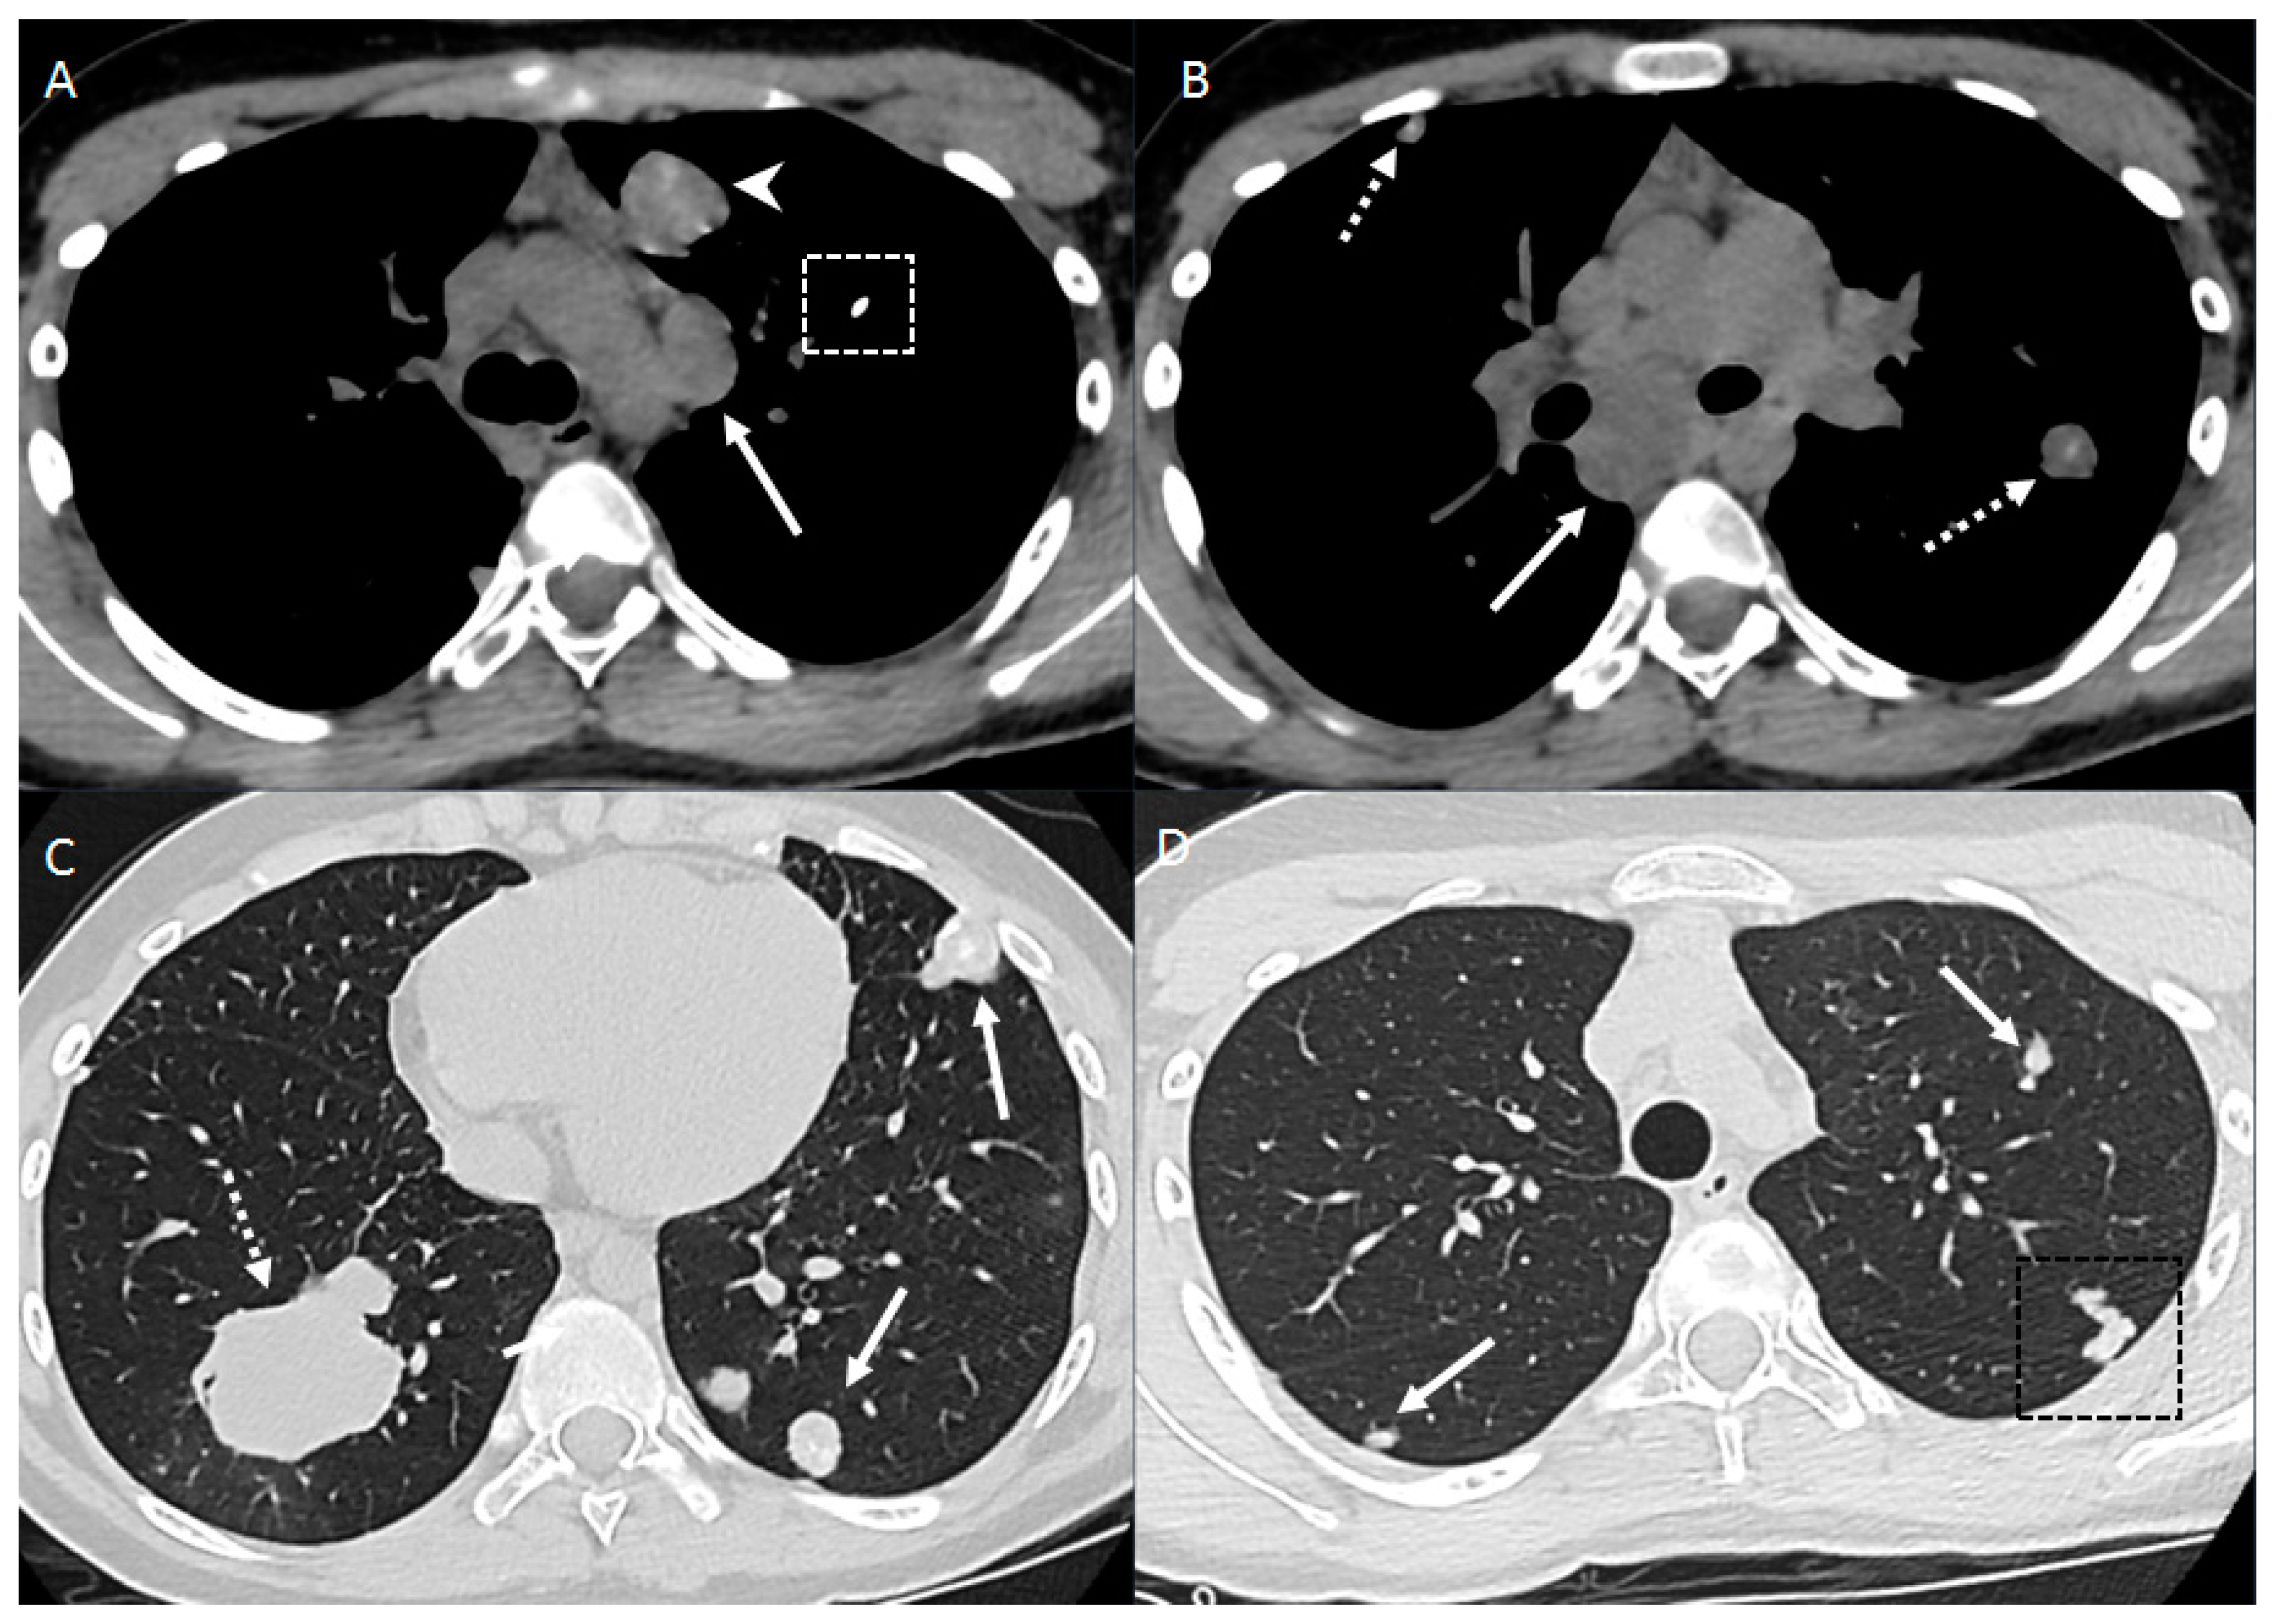

2.1. Parenchymal Metastasis

2.2. Vascular Metastasis

2.3. Endobronchial Metastasis

2.4. Lymphangitic Carcinomatosis